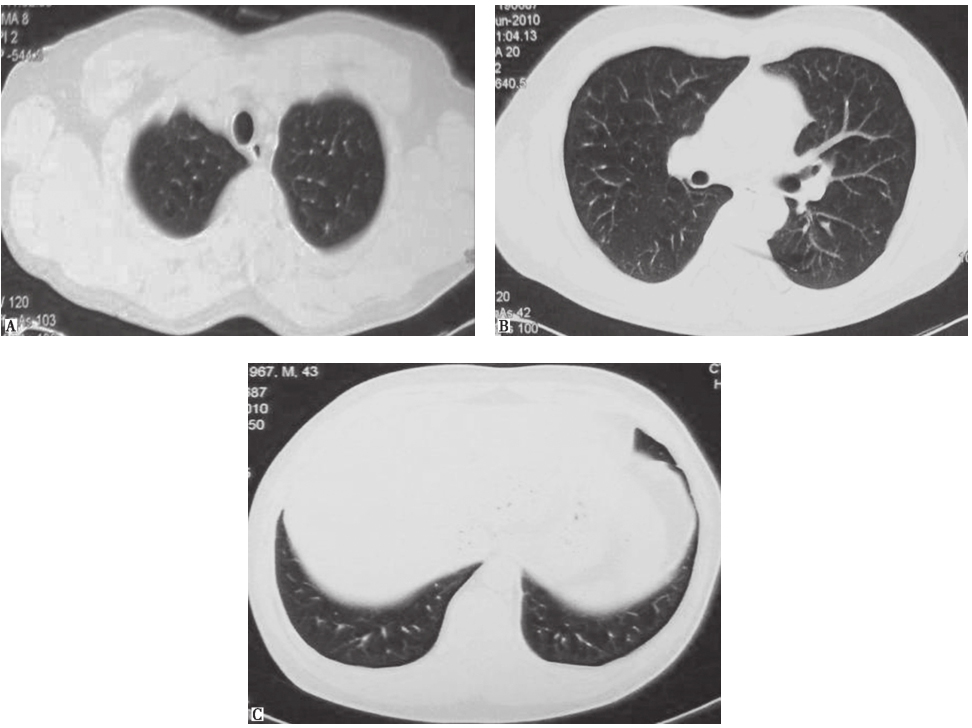

鉴于患者临床症状不重,无肺外系统受累,建议患者严格戒烟(包括被动吸烟)。患者在严格戒烟1个月后,症状逐渐减轻;3个月后复查胸部CT见双肺结节及空洞明显减少(图3);严格戒烟6个月后复查胸部CT显示双肺散在微小结节进一步减轻、减少(图4)。

图4严格戒烟6个月后复查胸部CT表现